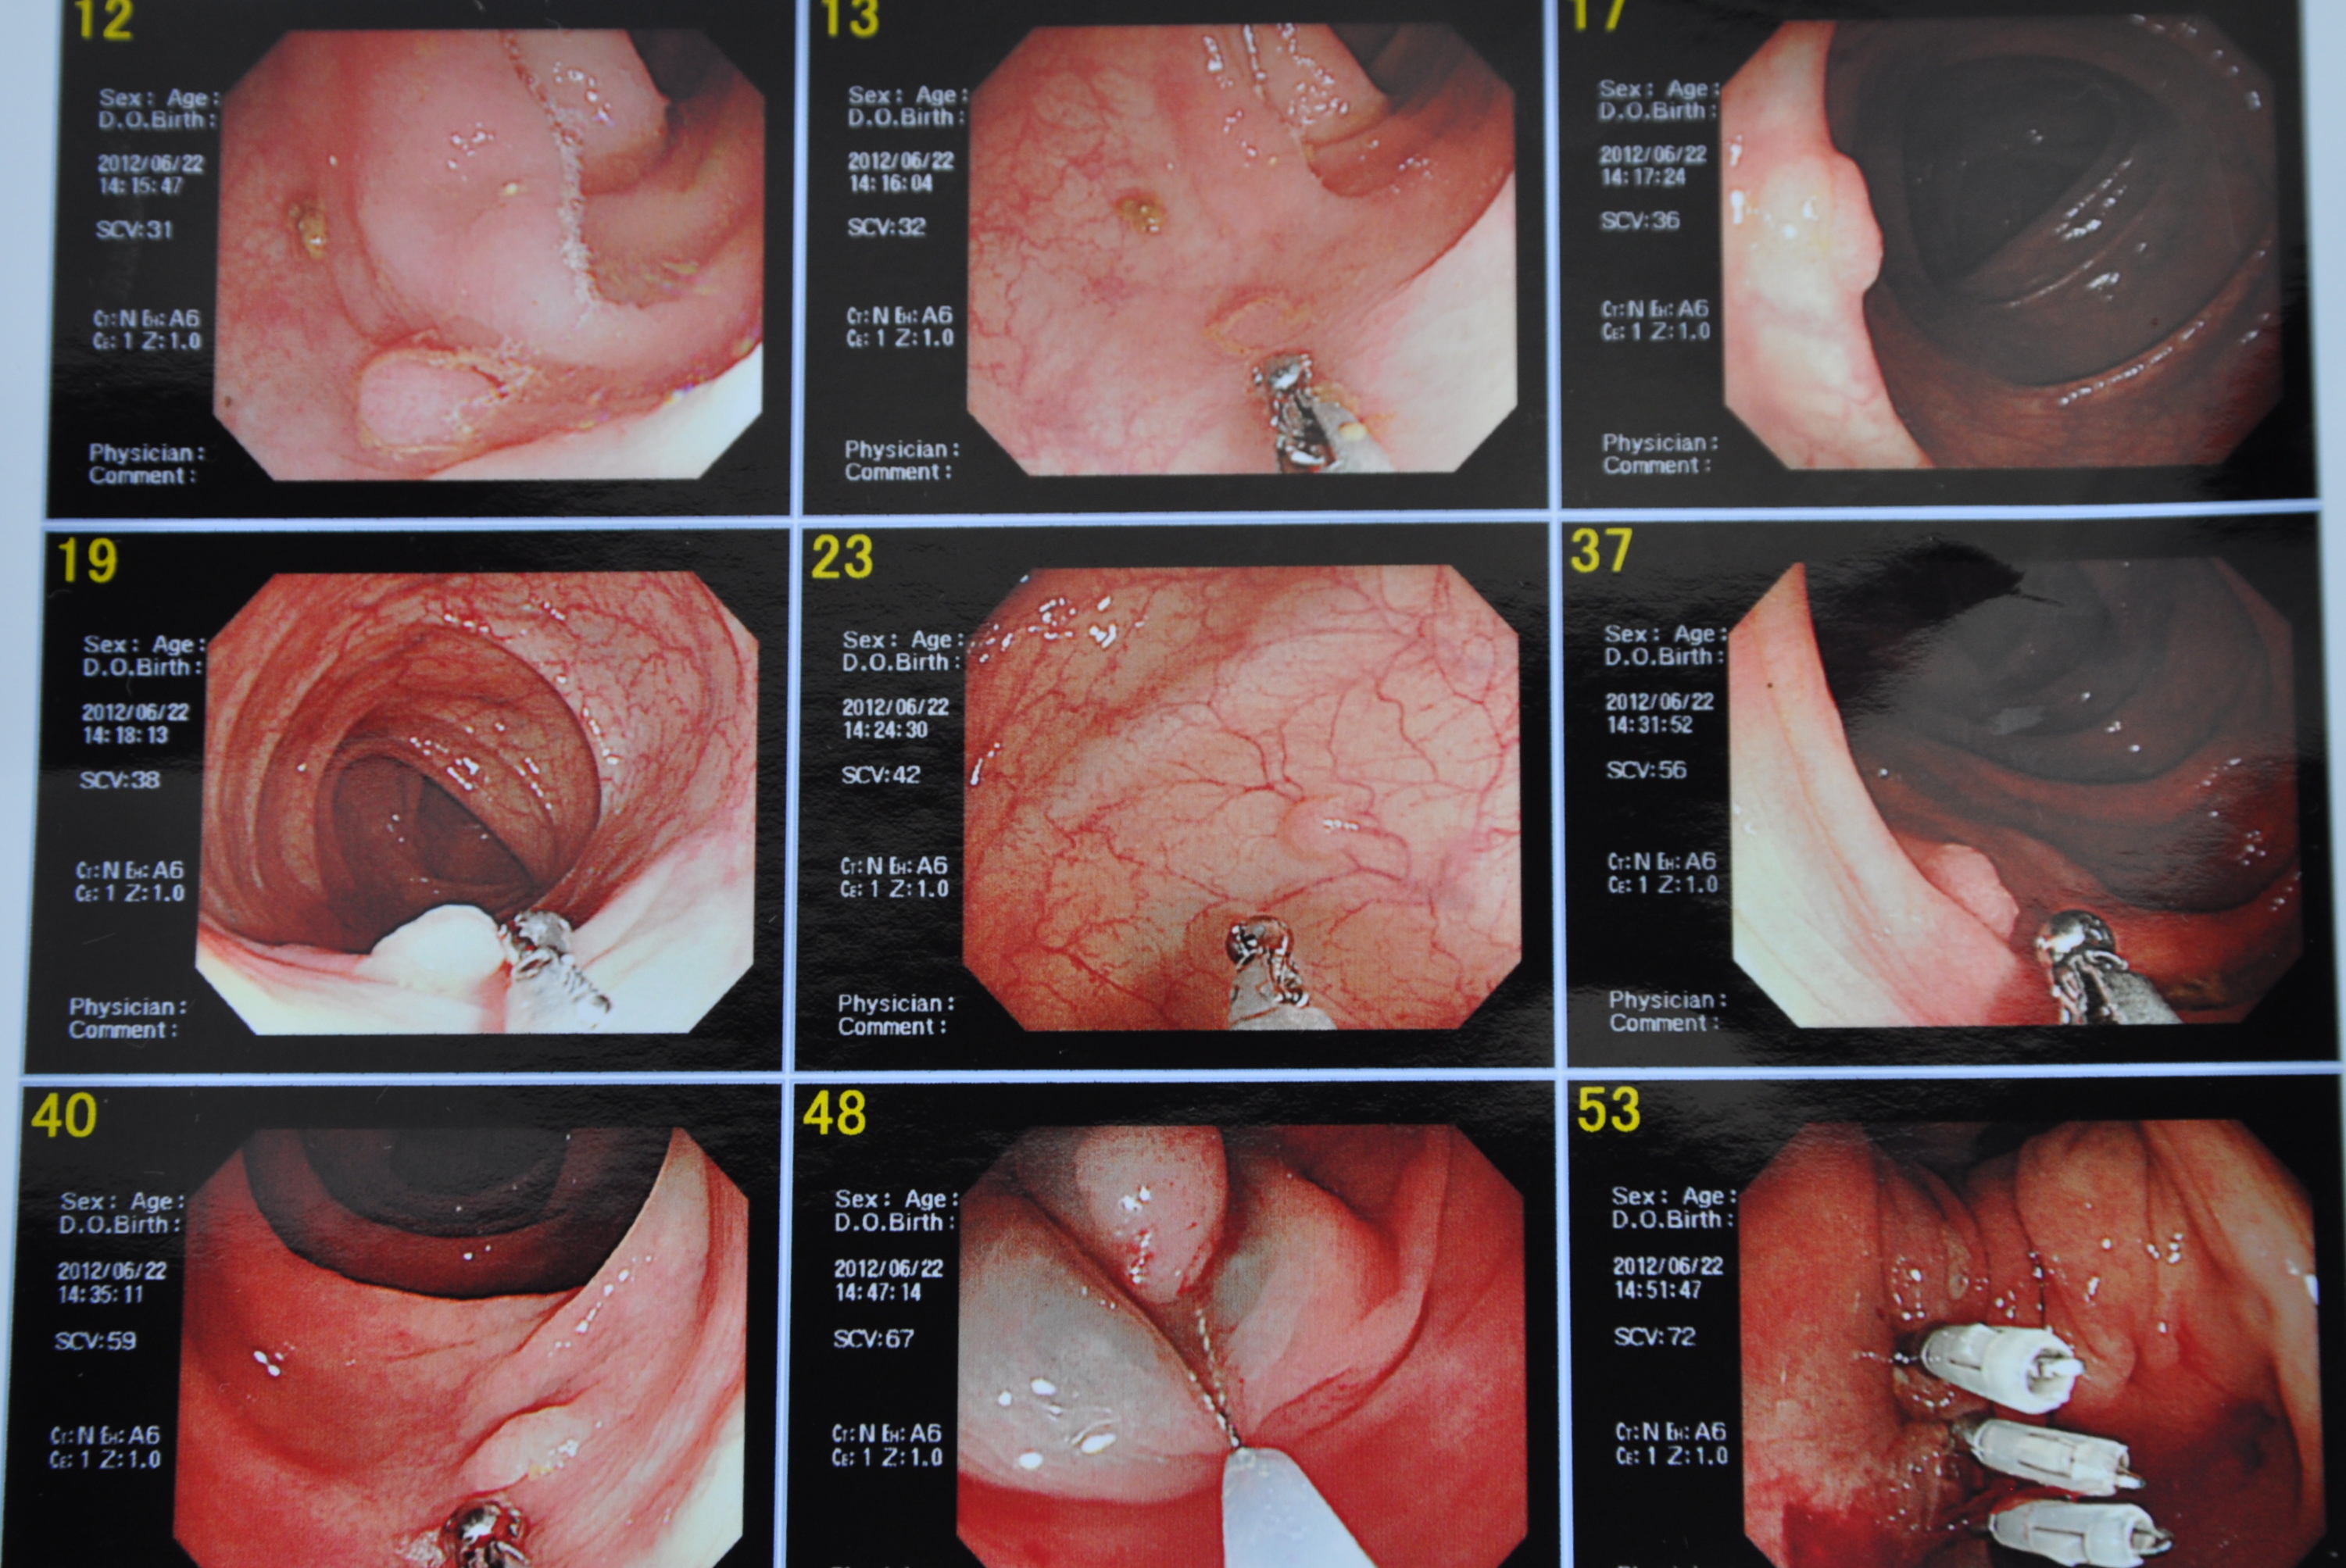

Travel log along my colon. Getting ready to snip minor offenders. 48 shows electrical snare being wound around big boy polyp.

Kubota-sensei progresses up my colon occasionally halting to snip off some junior polyps until he comes to the big boy polyp. The technique is to inject what he calls ‘blue water’ in the tissue under the polyp and by so doing elevate and expose the the object of desire. An electrical snare is then wound around it and the offending growth is burnt off. The wound is then closed with clip things that are part of the tool kit.